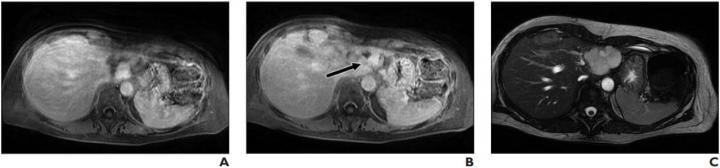

Lesion was originally reported as indeterminate enhancing mass, and outside report recommended biopsy. Classic features of benign hemangioma are shown. Error was attributed to faulty reasoning. A, Axial MR image obtained 5 minutes after contrast agent administration shows peripheral nodular discontinuous enhancement. B, Axial MR image obtained 10 minutes after contrast agent administration shows centripetal progression of enhancement (arrow). C, Axial fast imaging employing steady-state acquisition (FIESTA) MR image shows lesion is homogeneously hyperintense compared with liver parenchyma. Image courtesy of American Roentgen Ray Society (ARRS), American Journal of Roentgenology (AJR)

The most common error type contributing to both overall and primary discrepancy was faulty reasoning (a cognitive error characterized by misidentifying an abnormality), which occurred in 34.3% of the total discrepancies (95% CI, 29.0- 40.0%) and 37.8% of the primary discrepancies.